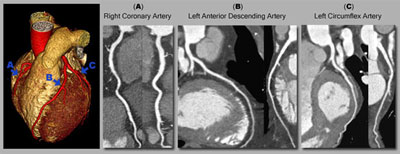

سی تی آنژیو چیست؟

سی تی آنژیو (CT Angio) یک روش تصویربرداری پزشکی است که از تکنولوژی سی تی اسکنر برای تولید تصاویر سه بعدی از عروق و عروق خونی استفاده میکند. در این روش، یک ماده حاجب به پرتو X به بیمار تزریق میشود تا عروق بدن را بصریسازی کند و اجازه دهد تا اندازه، شکل، و وضعیت عروق بررسی شود.